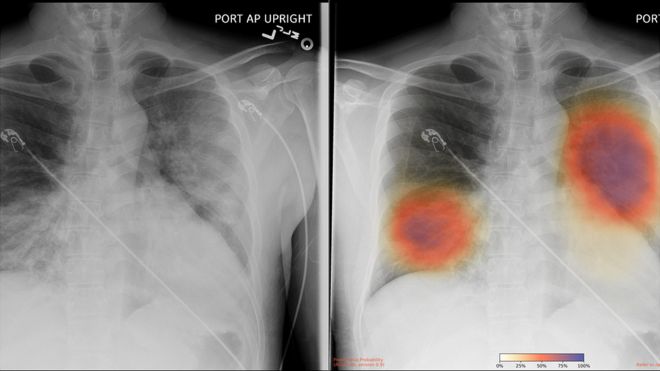

However, thanks to the pandemic, a few British hospitals are now rolling out AI tools to help medical staff interpret chest X-rays more quickly. For instance, staff at the Royal Bolton Hospital, are using AI that has been trained on more than 2.5 million chest X-rays, including around 500 confirmed Covid-19 cases.

It has been running automatically on every chest X-ray the hospital has carried out for about a week, says Rizwan Malik, a radiology consultant at the hospital. This means more than 100 patients will have had X-rays analysed by the system to date, he estimates. In this case, the algorithm is designed to look for possible signs of Covid-19, such as patterns of opacity in the lungs.

The BBC understands that two other NHS hospitals are currently using a different tool, which detects abnormalities in lung X-rays. A spokeswoman for Behold.ai, which developed the system, did not name the hospitals involved.

However, she said the software has so far analysed the scans of 147 patients with suspected Covid-19. It correctly classified the scans as “normal” or “abnormal” in more than 90% of cases.